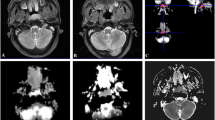

An example of temporal lobe necrosis detected by MRI is shown in Fig. 1.

Magnetic resonance (MR) imaging shows right temporal lobe necrosis in a 40-year-old woman with nasopharyngeal carcinoma at 3.5 years after radiotherapy. a Axial T1-weighted image shows right temporal lobe necrosis (arrow head) and brain edema (arrow); b axial T2-weighted image shows right temporal lobe necrosis (arrow head) and brain edema (arrow); b, c T2-weighted image shows right temporal lobe necrosis (arrow head) and brain edema (arrow); d, e coronal T2-weighted image shows right temporal lobe edema (arrow); f contrast-enhanced axial T1-weighted image obtained with fat suppression shows contrast enhancement in right temporal lobe necrosis (arrow head) and brain edema (arrow)